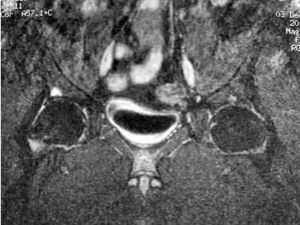

La afectación inflamatoria se manifestó, en todos los casos, como hiperintensidad en secuencia STIR y captación de contraste en secuencias T1. Doce pacientes presentaron afectación inflamatoria en la columna, ASI o caderas (figs. 1, 2 y 3).

Fig. 3.--SE T1 con supresión grasa y contraste paramagnético. Se aprecia captación de contraste en acetábulo derecho.

No hemos encontrado tampoco en la literatura ninguna referencia a la demostración de afectación inflamatoria en la EA en articulaciones coxofemorales. Dicha afectación se considera un factor de mal pronóstico en la enfermedad. Hasta ahora la valoración de la articulación de la cadera se llevaba a cabo, como ocurría con las ASI, mediante la radiografía simple. Dicha técnica, como ya hemos visto, no es sensible al cambio hasta pasados varios meses tras la instauración de los síntomas1,4. Sería útil poder detectar la afectación de cadera de manera precoz, ya que se podría instaurar un tratamiento más agresivo con antelación. En nuestro estudio hemos mostrado cómo también es posible detectar cambios en las articulaciones coxofemorales mediante RM, por lo que creemos que el estudio inicial mediante RM de un paciente afecto de EA debería incluir, desde el comienzo, las articulaciones coxofemorales.